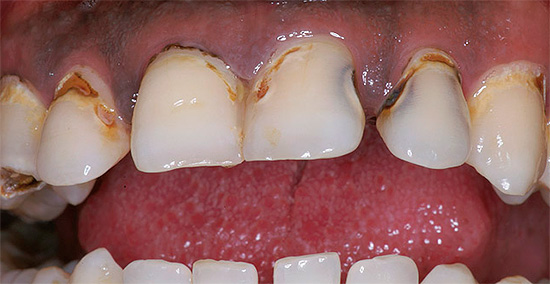

Se houver um orifício no esmalte (cavidade), definitivamente não será possível curar um dente sem obtê-lo. Em muitos casos, essas lesões de cárie que só podem ser tratadas por um dentista se apresentam como manchas marrons ou pretas distintas.

- Remoção de cárie ou tártaro em casa com uma lixa ou um arquivo. Nessas situações, o paciente às vezes até sente dores intensas, mas continua a "curar" (ou melhor, destruir) o esmalte, facilitando assim a derrota da dentina localizada sob ele, mais vulnerável à cárie.

- Tentativas de limpar cáries com uma agulha simples. Essa abordagem nunca produz um resultado duradouro - mesmo que você consiga limpar a área escura, a destruição (e pigmentação) neste local continuará.

- O uso de alvejantes e alvejantes para remover manchas escuras nos dentes. Esse "tratamento" caseiro é muito perigoso devido à possibilidade de uma queimadura grave da mucosa oral, e é simplesmente inútil, pois não é possível clarear um dente por esses meios de maneira eficaz.